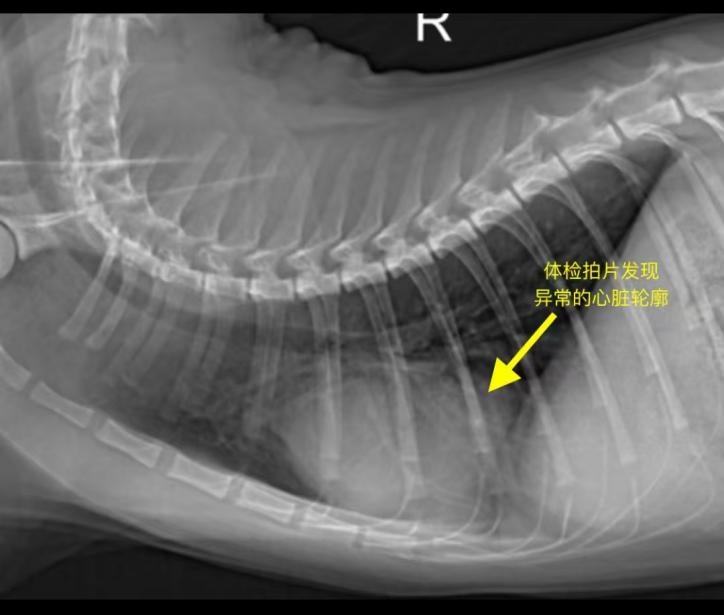

During a routine health check at our hospital, an abnormal cardiac silhouette was detected in the cat’s chest X-ray. Further echocardiography and abdominal ultrasound confirmed the diagnosis of pericardial diaphragmatic hernia (PDH). This condition is a rare congenital defect. Some cases remain asymptomatic for a long time, but if abdominal organs herniate into the pericardial cavity and cause compression, it may lead to cardiac dysfunction or severe respiratory distress.